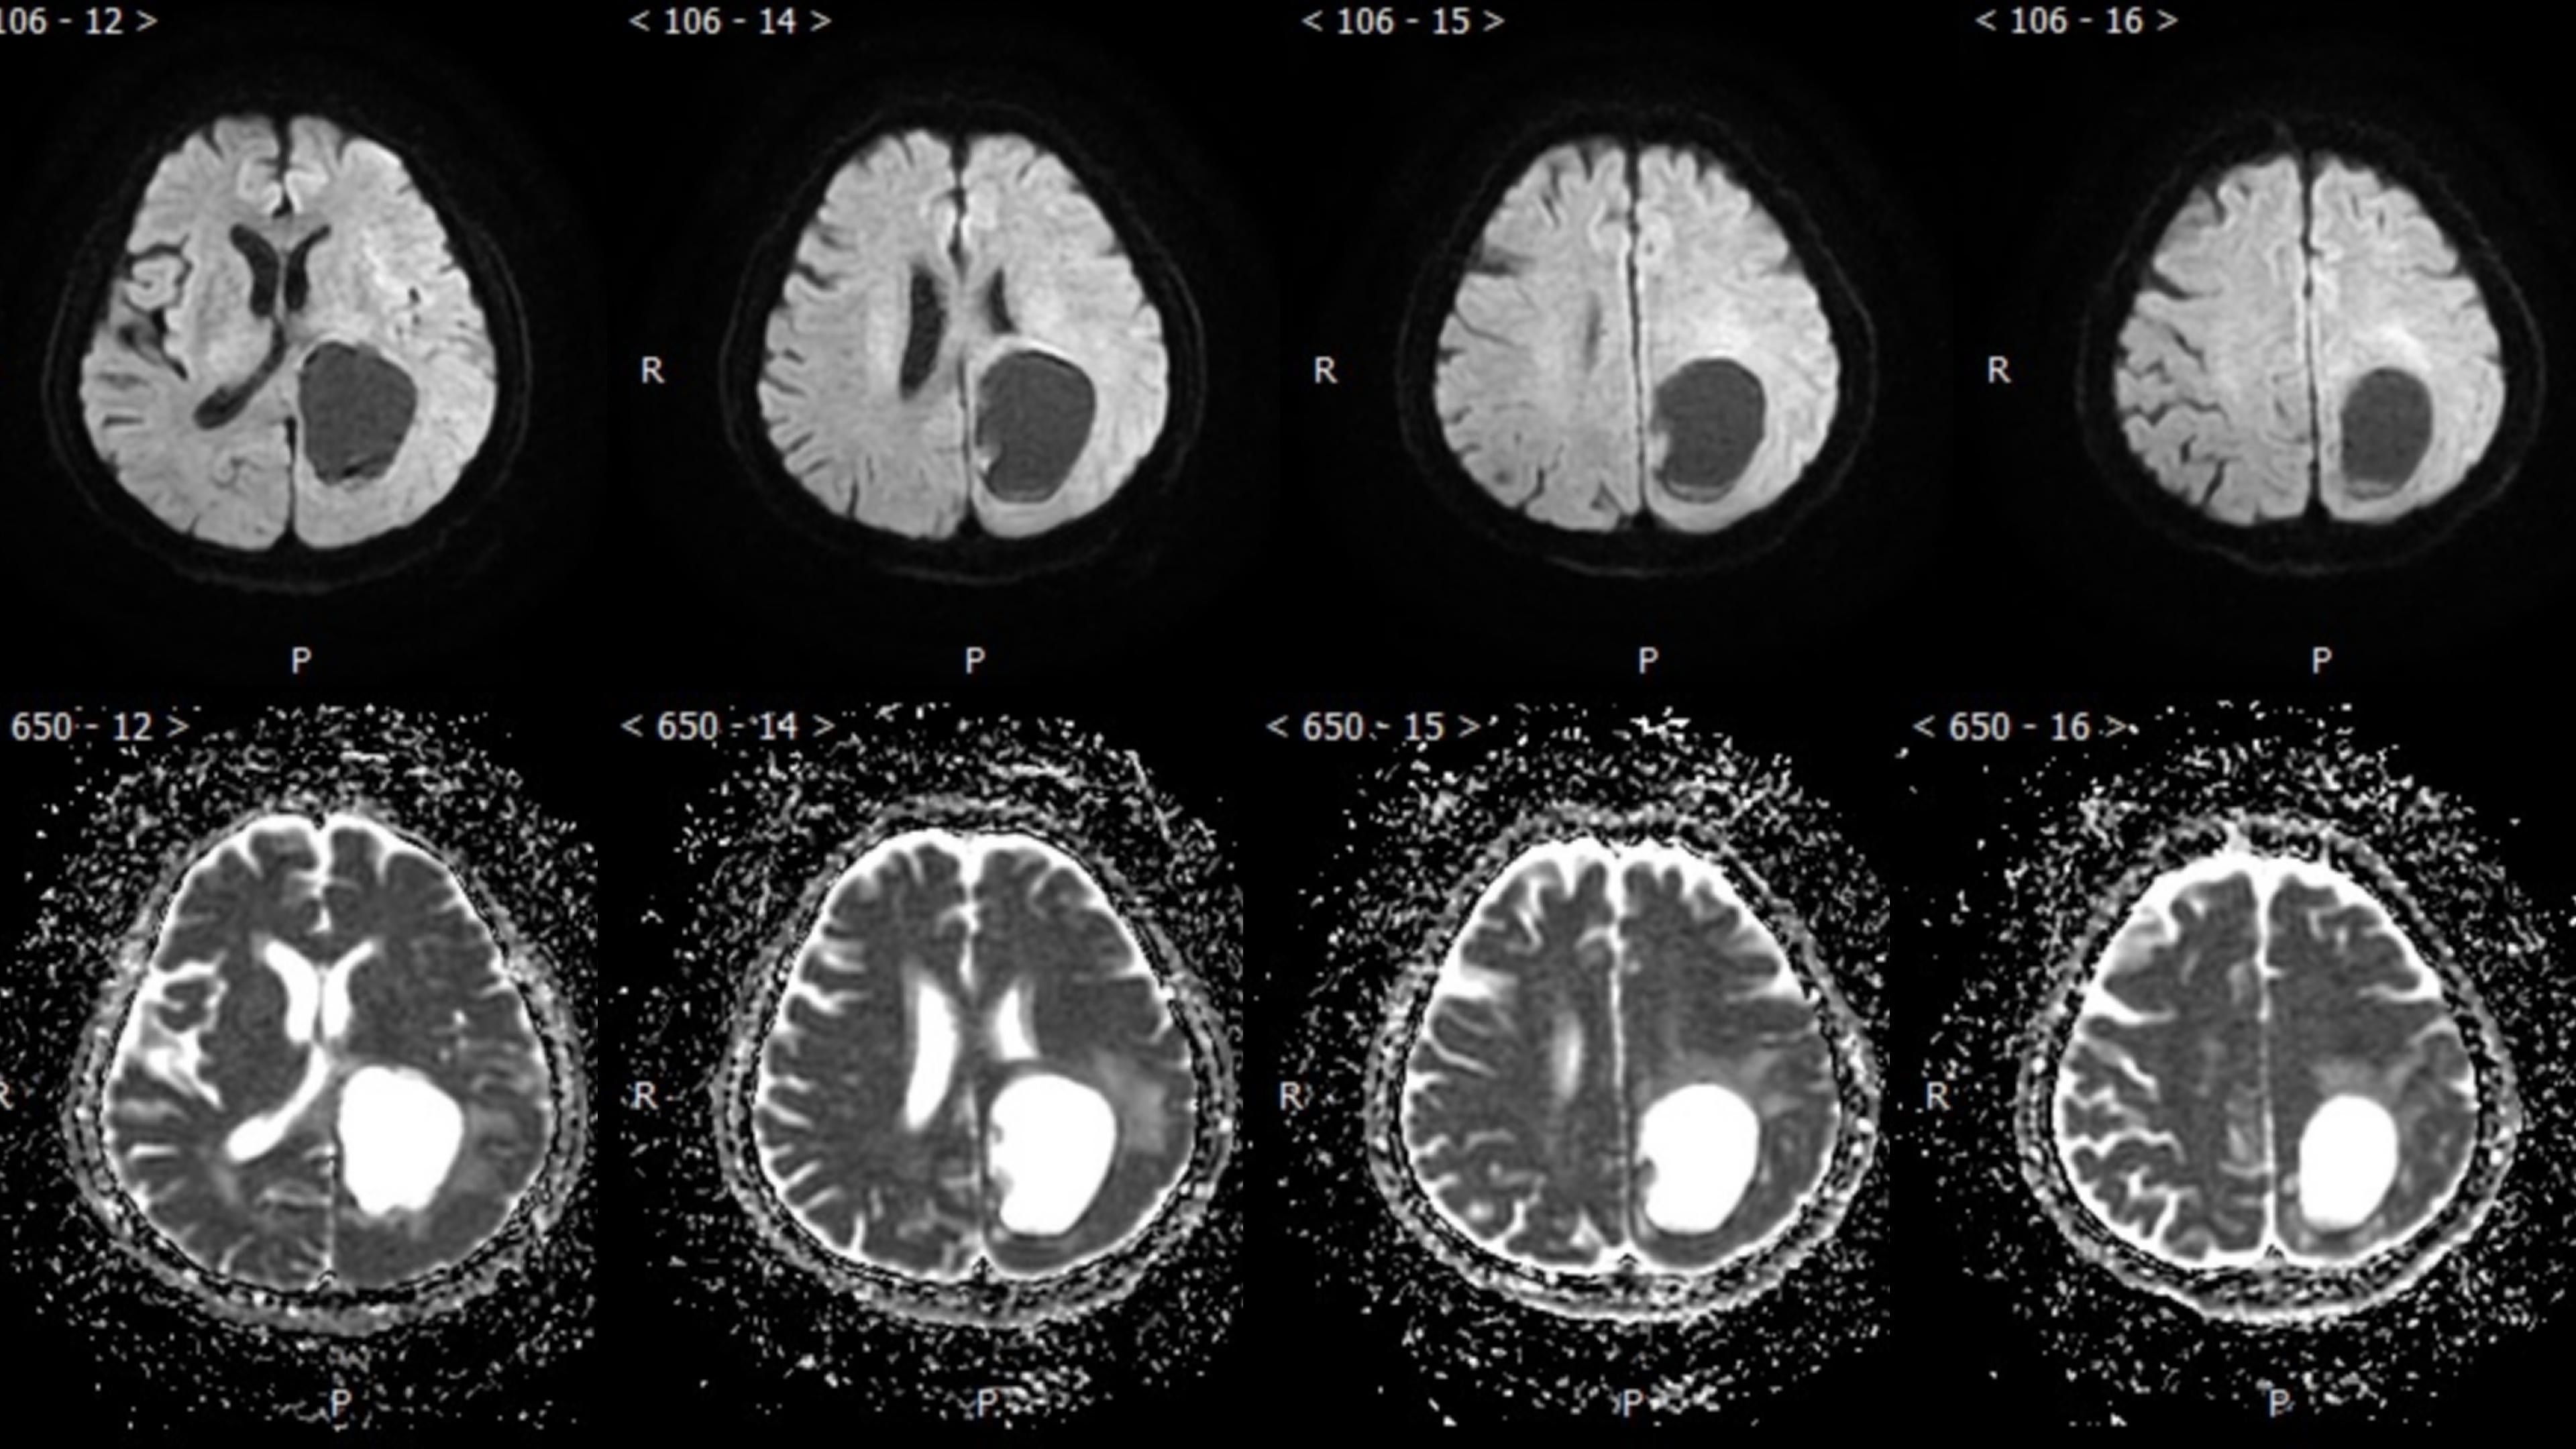

幕上毛细胞型星形细胞瘤(WHO Ⅰ级)